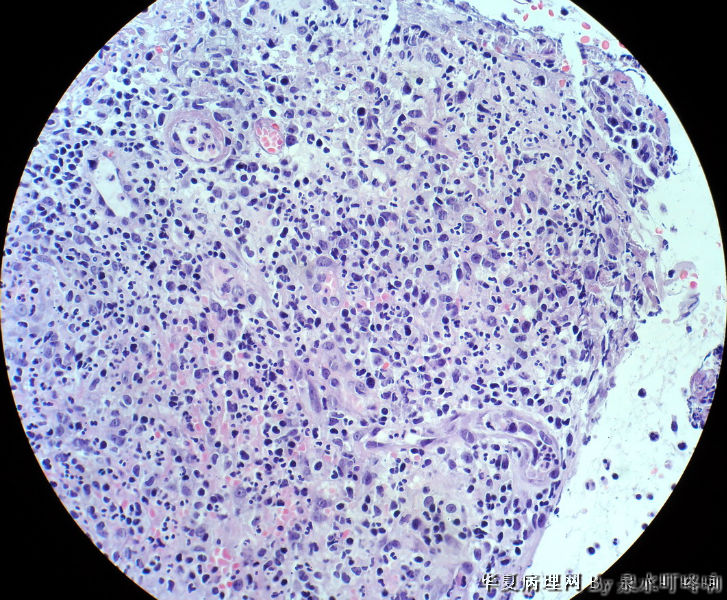

120071,男,64岁,左颊粘膜糜烂,面积约2×1.5厘米。